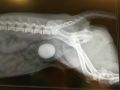

Av, min blære

8. November 2018